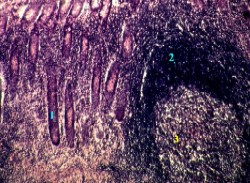

25.1.1.3. Препарат

I. Малое увеличение

1,а-б. Препарат - толстая кишка. Окраска гематоксилин-эозином.

1. На снимках - стенка ободочной кишки и в ней:

слизистая оболочка (I),

подслизистая основа (II) с сосудами (5),

мышечная оболочка -

внутренний циркулярный слой (III.В)

(гладкие миоциты срезаны поперёк),

наружный продольный слой (III.Г)

(очевидно, срез прошёл в области продольной ленты);

серозная оболочка (IV).

2.

а) В составе слизистой оболочки на снимке 1,а видны следующие структуры:

крипты (1); имеют форму простых трубчатых желёз;

собственная пластинка (2) - прослойки рыхлой соединительной ткани между криптами;

мышечная пластинка (3) - гладкие миоциты под криптами.